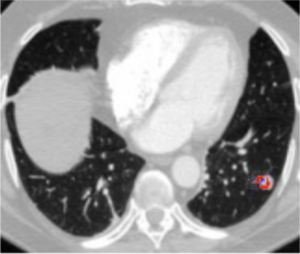

To measure the degree of alignment of the different methods, the researchers measure the fraction of the doctor-annotated area the model pays attention to.

In red: The doctor-annotated area.

In blue: The model's area of attention.

The researchers measure the black area divided by the blue area. In this example, the alignment score would be 25%. When we look at the results, we can see that the alignment scores of the different methods vary greatly:

Liu et al.'s method performs very well: On average, their model's attention area has a 75% overlap with the doctor-annotated area. No other method makes it past 10%! We can see that the +/- label massively distracts the other methods from paying attention to the correct areas of the image. We can see this in the following visualization: